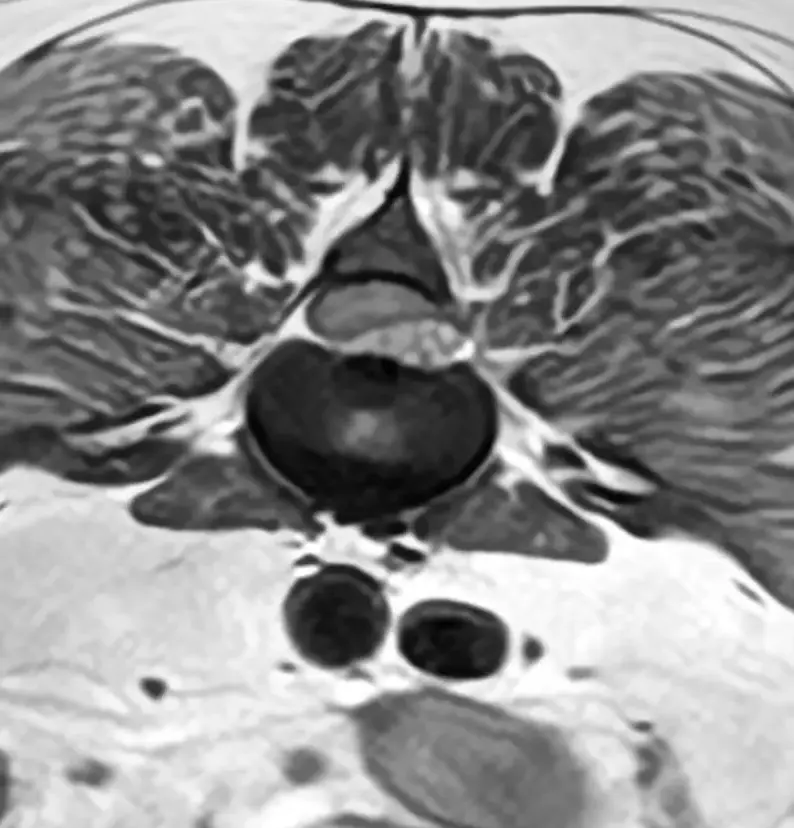

- 神経学的検査:歩行や反射の評価でグレードを判定

- 画像診断:

- MRI:最も確実。脊髄圧迫の程度と部位を確認

- CT:骨や椎間板の突出部位を確認

※CT検査だけでは圧迫部位の予測はついても脊髄の状態がわからないため、明らかな場合以外は単独で診断に用いることはありません。CT、MRI両方撮像できれば理想ですが、費用がネックです。

最も一般的な手術は「片側椎弓切除術(hemilaminectomy)」です。背骨の一部を削り、飛び出した椎間板物質を除去します。

外部医療機関でMRIを撮像してきてもらい、その画像を元に外科手術を計画します。